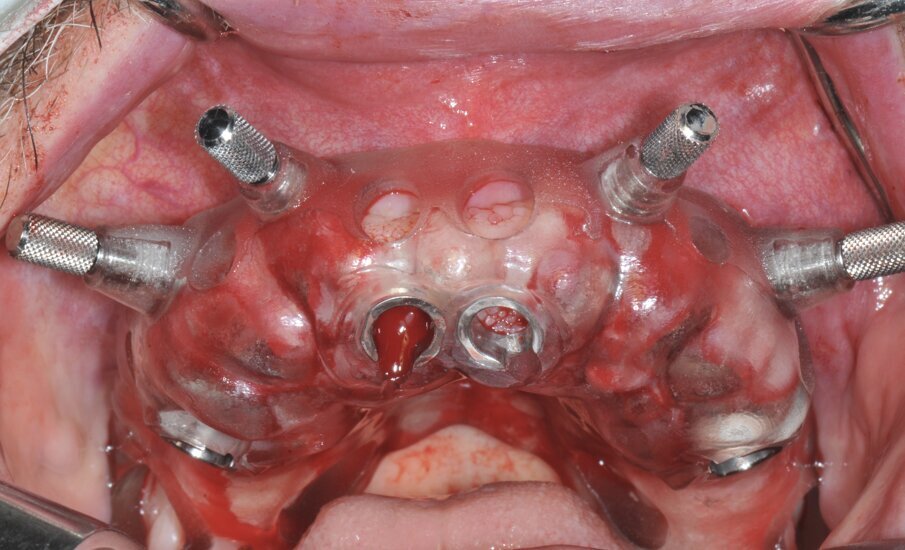

In prima fase, sono state scansionate entrambe le arcate, così da ottenere una registrazione occlusale e una dimensione verticale. Sono state scattate fotografie intra- ed extra-orali con precisi parametri, per visualizzare tutti i dati raccolti in un software di digital smile design. I file STL sono stati poi sovrapposti ai file DICOM della TC Cone Beam con un software dedicato. Tramite un software di chirurgia guidata è stata poi stabilita la posizione dei 4 impianti post-estrattivi, da posizionare con l’ausilio di due dime chirurgiche differenti (Fig. 2). La prima dima ad appoggio dentale è stata prodotta al fine di creare le sedi per l’alloggiamento dei pin di posizione. La seconda dima fissata con pin nella posizione precedentemente determinata, presenta le cannule per la preparazione del sito e l’inserimento implantare (Figg. 3a, 3b). Sulla base della stessa ceratura è stata poi prodotta una protesi totale fissa provvisoria in PMMA rinforzata con una struttura in titanio, su cui è stata riprodotta la dimensione verticale originaria del paziente.

Fig. 3a_Dima chirurgica ad appoggio dentale e mucoso per il posizionamento dei pin di posizione.

Dopo l’estrazione degli elementi residui, sono quindi stati inseriti i 4 impianti mono-componente con MUA integrato FIXO (OXY Implant Dental System, Colico, Italia) con un torque d’inserzione maggiore di 35 N/cm. Gli alveoli post-estrattivi sono stati riempiti con osso bovino deproteinizzato (Bio-oss Geislich Wholusen CH) così da ridurre il rimodellamento osseo12. La gestione dei tessuti molli è stata ottenuta mediante un innesto connettivale con tecnica bilaminare a livello dell’impianto in posizione 11. Sono stati avvitati gli abutment provvisori direttamente alla piattaforma protesica integrata per poter procedere poi a un corretto posizionamento della struttura protesica grazie a un incollaggio intraorale. La protesi è stata fissata ai monconi provvisori con una resina composita auto foto polimerizzabile (Relyx Unicem 2 3M Minnesota USA) direttamente in bocca, ottenendo così la passivazione della stessa (Figg. 4a, 4b).

Fig. 4a_Visione occlusale degli impianti posizionati tramite dima chirurgica.